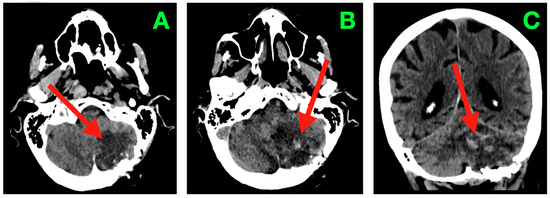

Advanced neuroimaging approaches are being used as valuable additional tools in characterizing brain lesions alongside conventional imaging techniques. The importance of advanced neuroimaging approaches is that they can provide information regarding the underlying pathophysiology of various brain lesions. Currently, both computed tomography (CT) and magnetic resonance imaging (MRI) include modern neuroimaging techniques, like dual-energy CT, photon-counting CT, perfusion MRI, functional MRI, diffusion-weighted MRI, diffusion tensor imaging, MRI spectroscopy, and MRI fingerprinting. Advanced approaches like radiomics analysis applied to CT and MRI images are increasingly being used for brain lesion characterization. Combining advanced neuroimaging approaches along with artificial intelligence techniques such as machine learning and deep learning algorithms will further promote and accelerate the adaptation of advanced neuroimaging methods in routine clinical neuroimaging. This Special Issue, entitled "Brain/Neuroimaging 2025", will include the application of advanced neuroimaging approaches for the characterization of brain lesions (tumors, demyelinating changes, ischemic stroke, hemorrhage, and infectious lesions) and neurodegenerative disorders, as well as the monitoring of treatment-induced brain lesions.